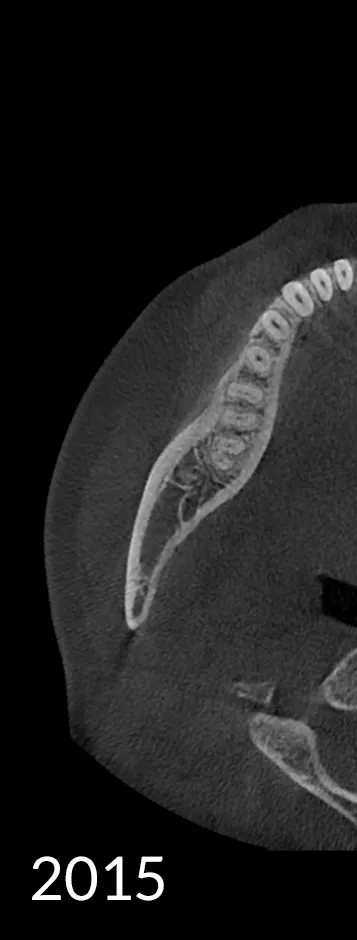

HDX CYOPTIX is our advanced imaging solution designed to deliver exceptional clarity and precision. As a continuously evolving software technology, CYOPTIX enhances image contrast and detail, supporting accurate diagnostics across various applications.

Since its inception, CYOPTIX has undergone continuous development. Our state-of-the-art image reconstruction algorithm now identifies the optimal value for each voxel, dramatically enhancing both contrast and sharpness for clearer, more reliable diagnostic outcomes.